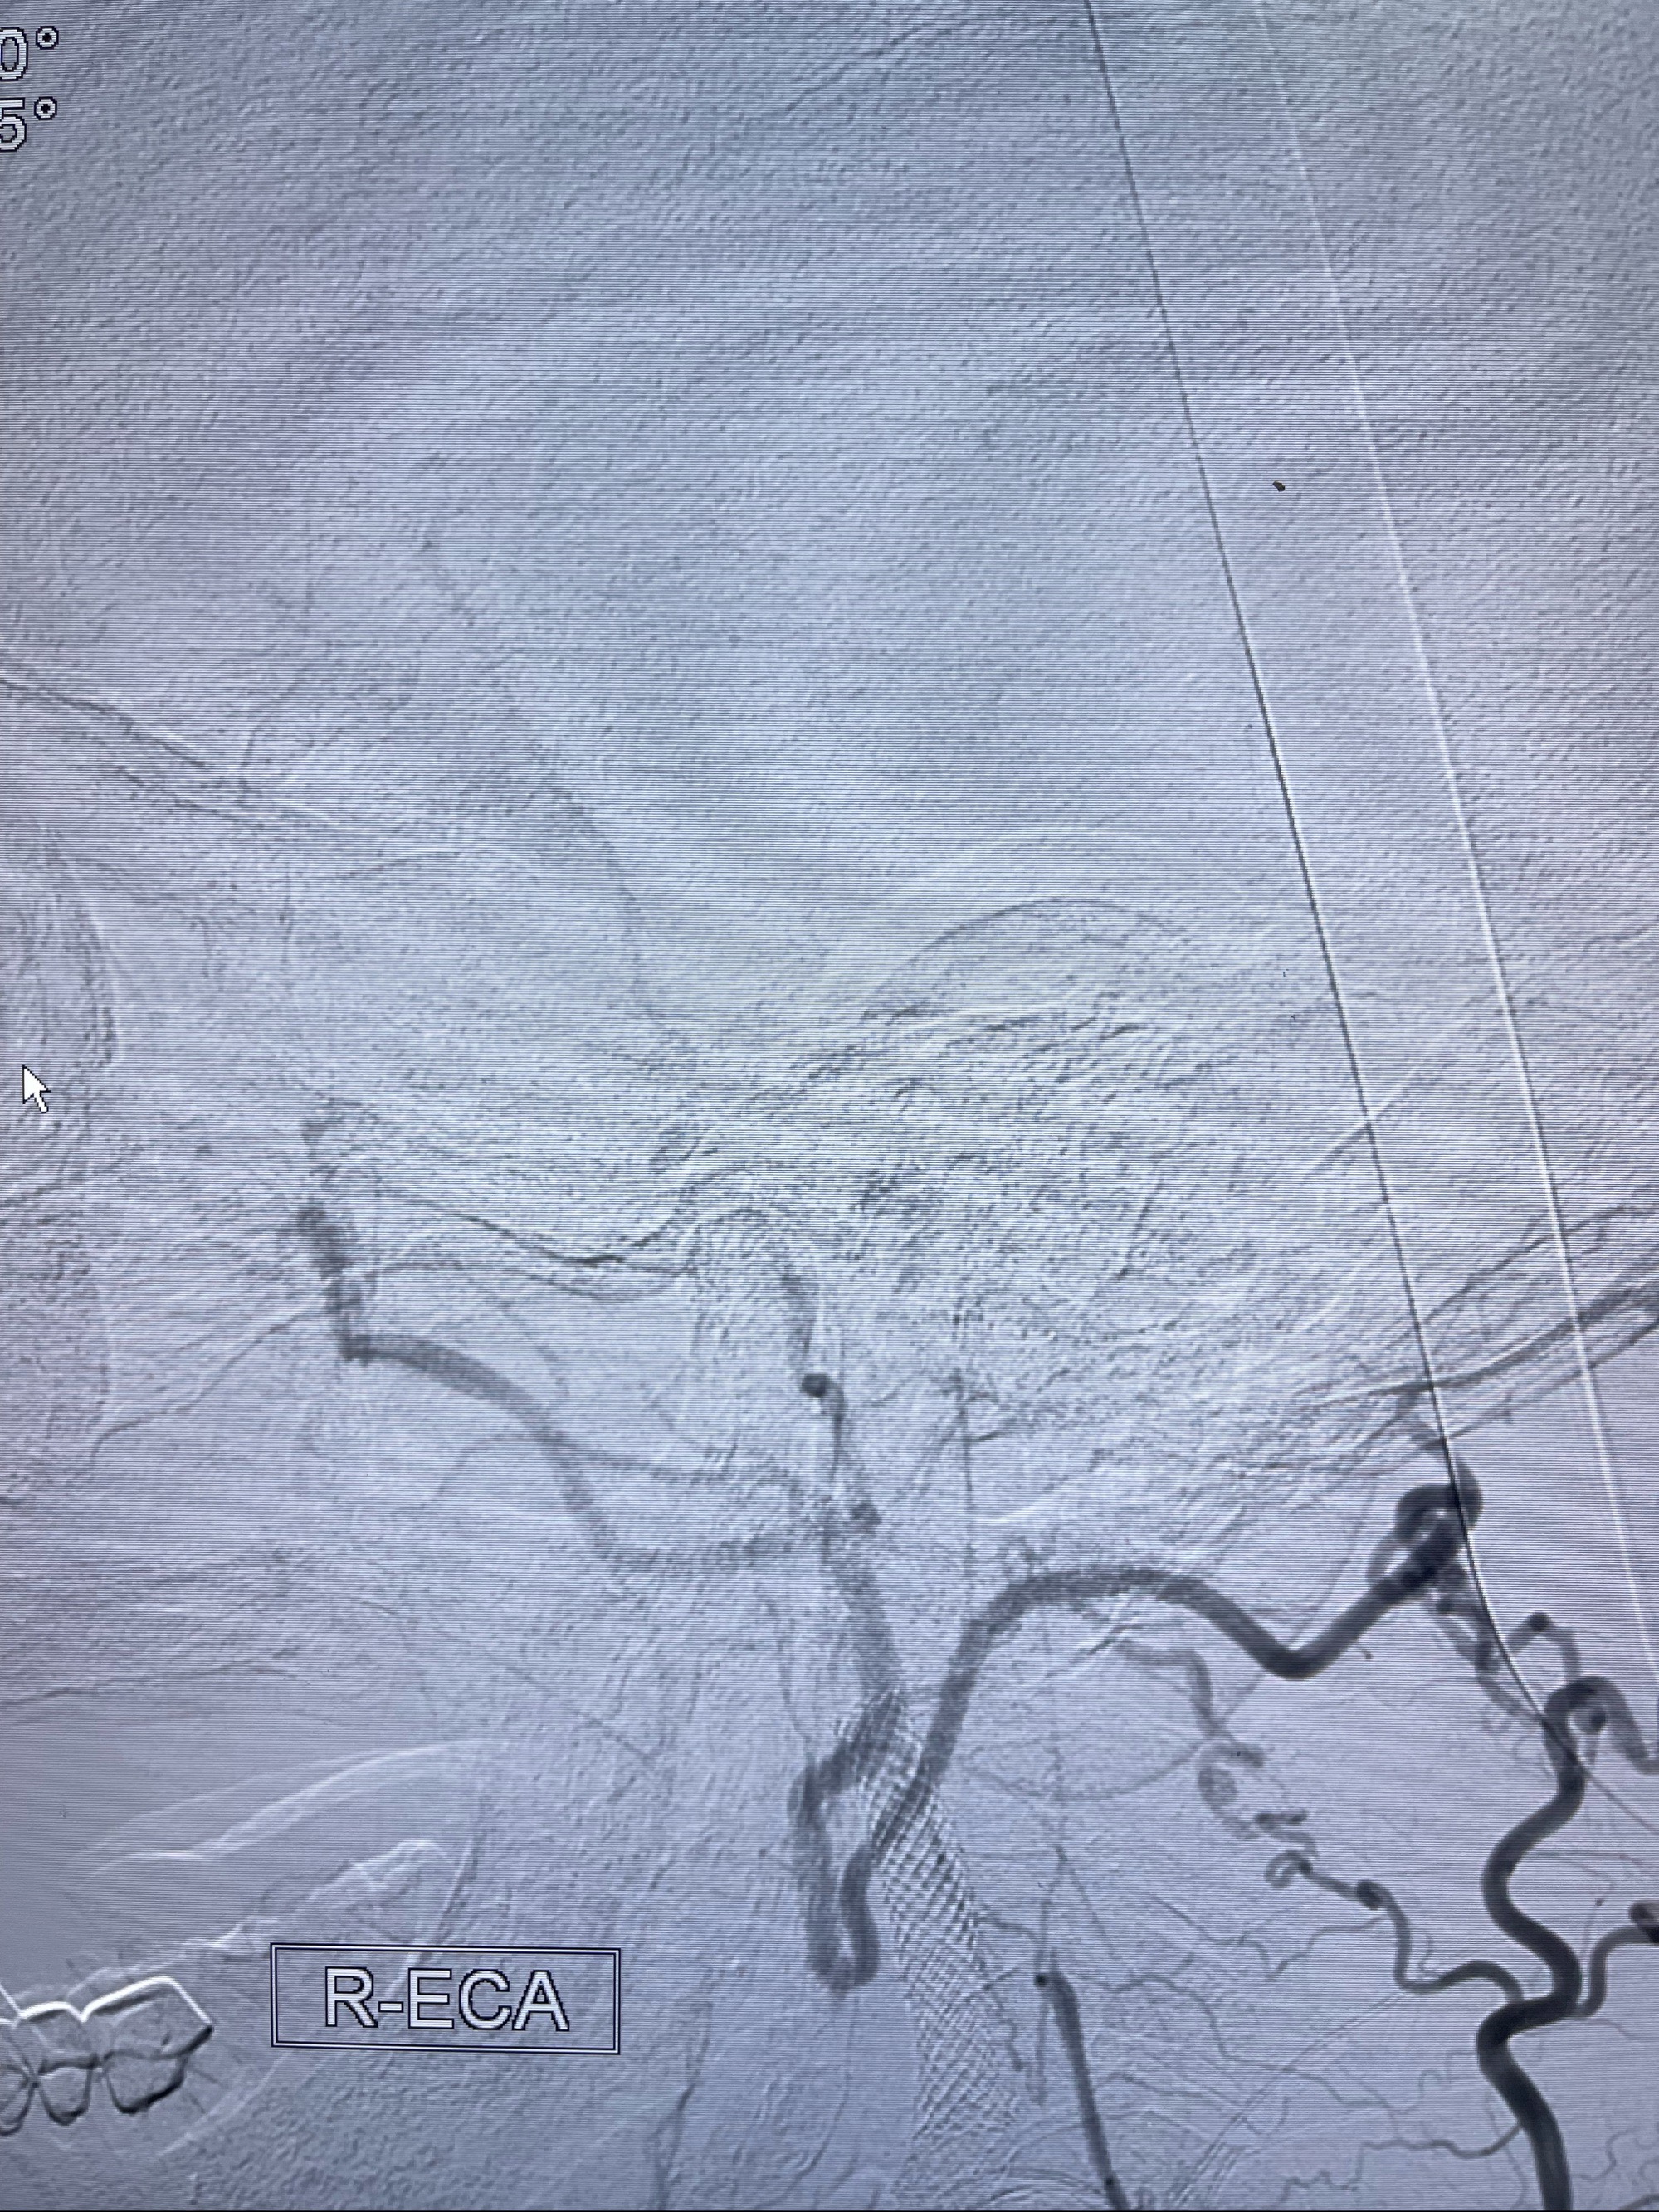

2023-07-10DSA:右侧颈内动脉岩骨段夹层伴中偏重度狭窄改变,左侧颈总动脉闭塞、右侧颈外动脉由右侧肋颈干甲颈干吻合代偿

箭头所示为颈内动脉岩骨段重度狭窄,结合MRI,考虑为肿瘤侵犯右侧颈内动脉

箭头以近至支架段管腔不规则狭窄

右侧椎动脉可见吻合代偿右侧颈外动脉